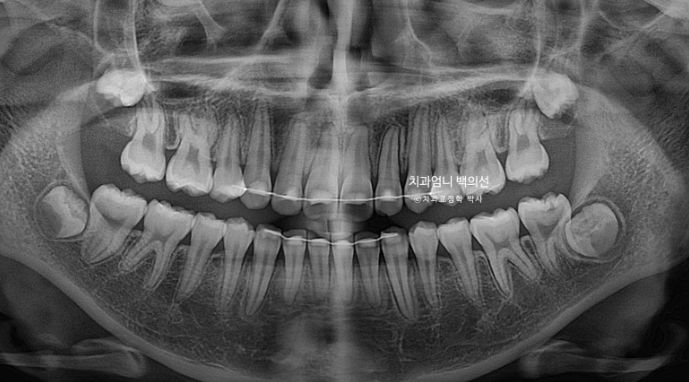

치근흡수는 없고 치근평행도는 좋습니다.

돌출이 위에만 국한되어 있어 위에만 작은어금니 2개 발치 후 교정하기로 했습니다.

1년 9개월 후 치료를 마쳤습니다.

교합은 좋습니다.

간혹 작은어금니 발치교정은 4개를 빼야 교합이 맞지 않나에 대한 질문을 듣는데 위에만 돌출인 경우 위에만 2개 빼는 교정도 좋은교합으로 마무리 되는 교정이랍니다.